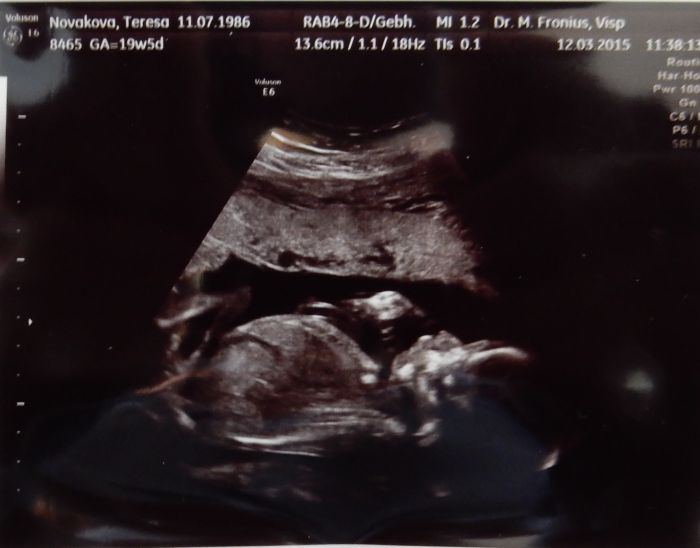

Ahoj holky, tak hlásím prohlídku ve 21tt. Termín nám zůstává stále na 1.8., prcek váží 340g a má se čile k světu. Krásně si skoro celou dobu cucal palec a prý máme fotogenické dítě :-) Tlak opět trošku vyšší, doufám, že se to nebudu zhoršovat. Zatím jsem ještě v toleranci, ale... No a váha... přemýšlím, kde jsou ta kg, mám nahoře kolem 4,5kg. Ani bych to neřekla. Jinak máme vše v naprostém pořádku. A dneska jsem si to konečně užila tu prohlídku. Bylo to super. Dostali jsme další průkazku, kdyby jsme náhodou rodili tady. No a pokud ano, tak se prý musíme ve 30tt nahlásit v porodnici tady v nemocnici. Takže opravdu nevíme jak to provedeme. A co čekáme už taky víme

Tak jsme koupili ještě dvoje kalhoty a dvoje pidi ponožky, ať má to malý radost. Máme asi 8 fotek, tak aspoň dvě přikládám. Za chvíli se půjdu natáhnout a v posteli vás dočtu. Mám jen přidat trošku hořčíku, čím víc tím líp.